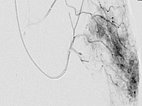

Particle embolization with spherical particles 250 micrometers in size via the microcatheter inserted superselectively into the tumor.

More tumor vessels with blush-like diffuse enhancement, typical of a vascular tumor / NICH. All these vessels must be selectively embolized to induce involution.

Further selective particle embolization. The embolization particles mixed with contrast medium remain in the tumor vessels.